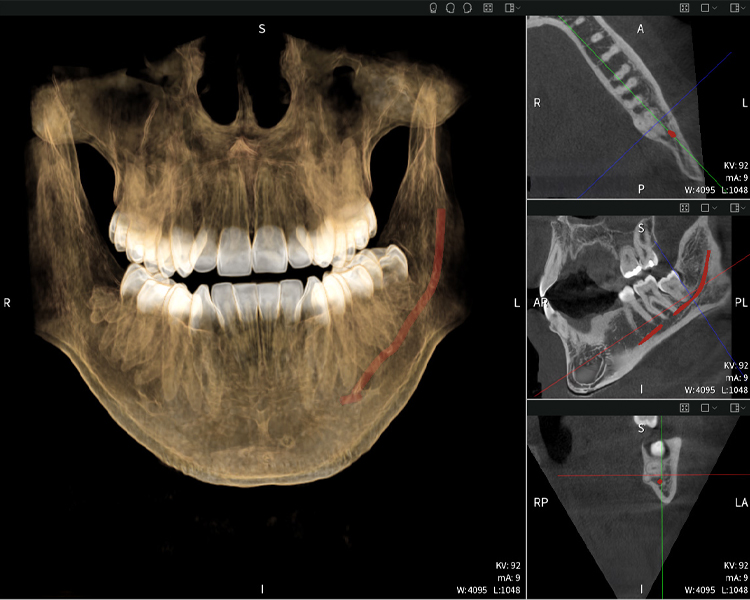

A continuación encontrarás un caso del Dr. med. dent. Oliver A. Centrella, en el cual las imágenes CBCT obtenidas con Seethrough Max proporcionaron información crucial sobre la anatomía compleja y la relación crítica entre las muelas del juicio y el nervio alveolar inferior. En este caso, existe una indicación para la extracción quirúrgica de las muelas del juicio.

Figura b: Resultados de imagen de Seethrough Max, sobre un fondo negro.

Las figuras b–d muestran varias vistas de una reconstrucción 3D de la mandíbula, proporcionando una visión general completa de la anatomía mandibular, la posición de los nervios en relación con los dientes y permitiendo evaluar la simetría y alineación dentaria.